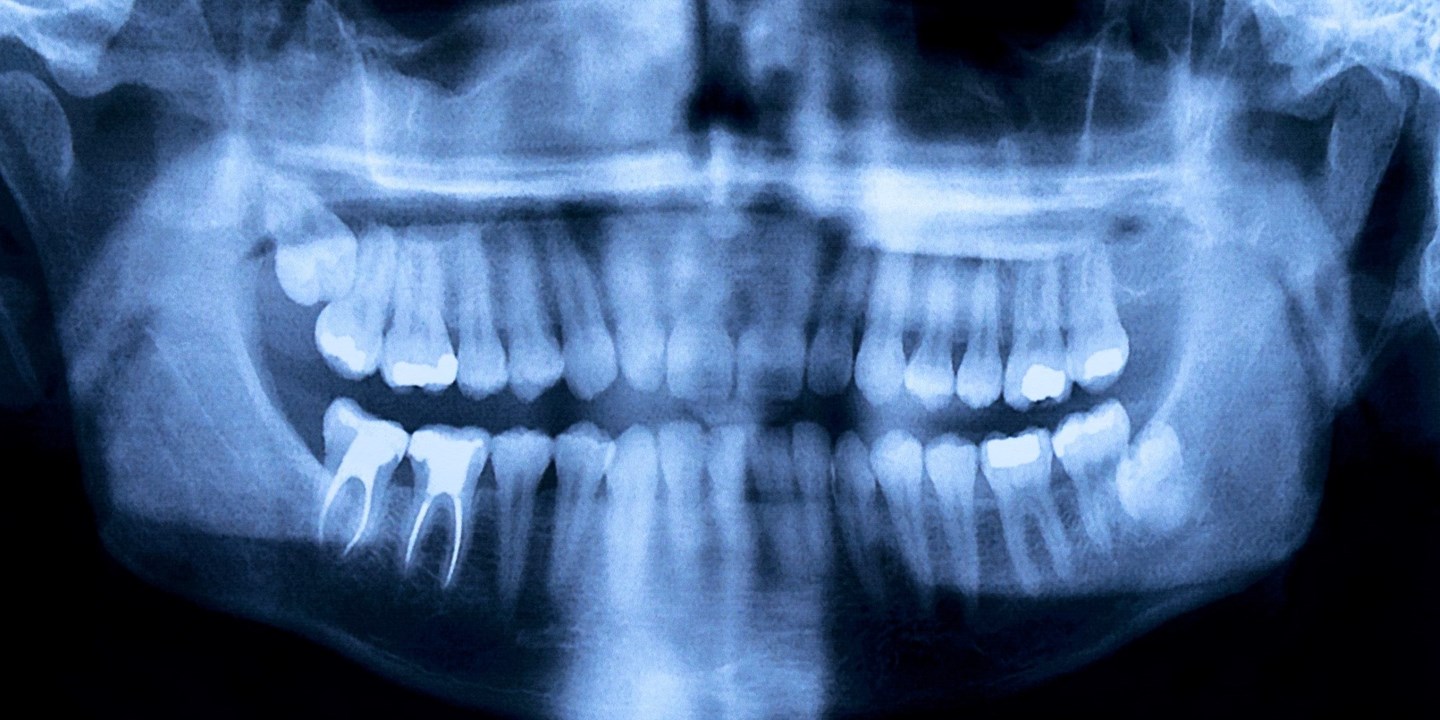

Det finns flera orsaker till att pulpan inuti tanden dör, bland annat karies, läckande fyllningar och tandgnissling.

En inflammation eller infektion inne i tanden innebär att pulpan är skadad. Besväras du av molande värk, känslighet för kyla och värme, svullnad och ömhet kan det vara tecken på en skadad pulpa.

Det är dock inte alltid du får symptom. En levande pulpa är förstås att föredra, men tanden går att rädda även om pulpan skulle dö. Lösningen är rotbehandling.